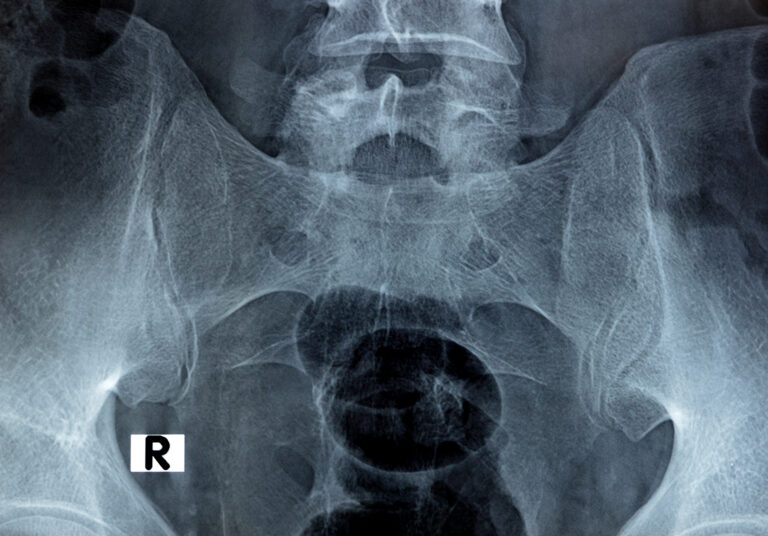

Mal di schiena

Il dolore lombare è una condizione molto frequente. Può avere diverse cause, come problemi muscolari, articolari o discali, e spesso limita le attività quotidiane.